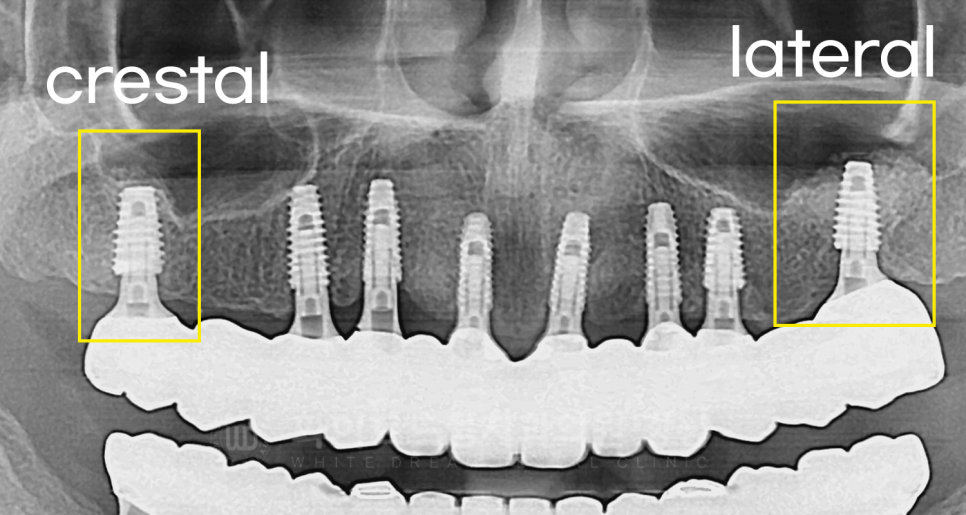

임플란트는 총 3회에 걸쳐 부분적으로 진행했습니다.

수술 1) 10번대 수술 (20.04.04)

16, 14, 13, 11, 21, 23, 24 번 임플란트를 식립했고,

이중 16번은 상악동 거상술 (crestal)을 이용하여 부족한 잇몸뼈를 보강했습니다.

수술 2) 20번, 30번대 수술 (20.04.18)

24, 26, 34, 36번 임플란트 식립과 lateral 방식의 상악동 거상술 수술을 진행했습니다.

수술 1차에서 16번 치아도 상악동 거상술을 진행했는데, 술식이 다르죠?

16번은 crestal 방식을 이용했고

24, 26번은 laterla 방식을 이용했습니다.

치료 후 x-ray를 보면 식립된 뼈의 양이 다른 것이 한눈에 보이실 겁니다.

잇몸뼈가 너무 얇거나 없는 경우,

구강 내 구조물로 인해 수술이 어려울 것으로 판단되는 경우는

lateral 방식을 이용하는데, 뺨쪽 잇몸에 창(window)을 내어 진행하는 방식입니다.

당연히 난이도는 crestral >>>>>>>>>>>>>>>>>lateral입니다.

(그래서 lateral 수술 경험이 많은 의사는 cesrtal 수술은 눈 감고도 한다.. 뭐 이런 말도 있답니다. ^^;)